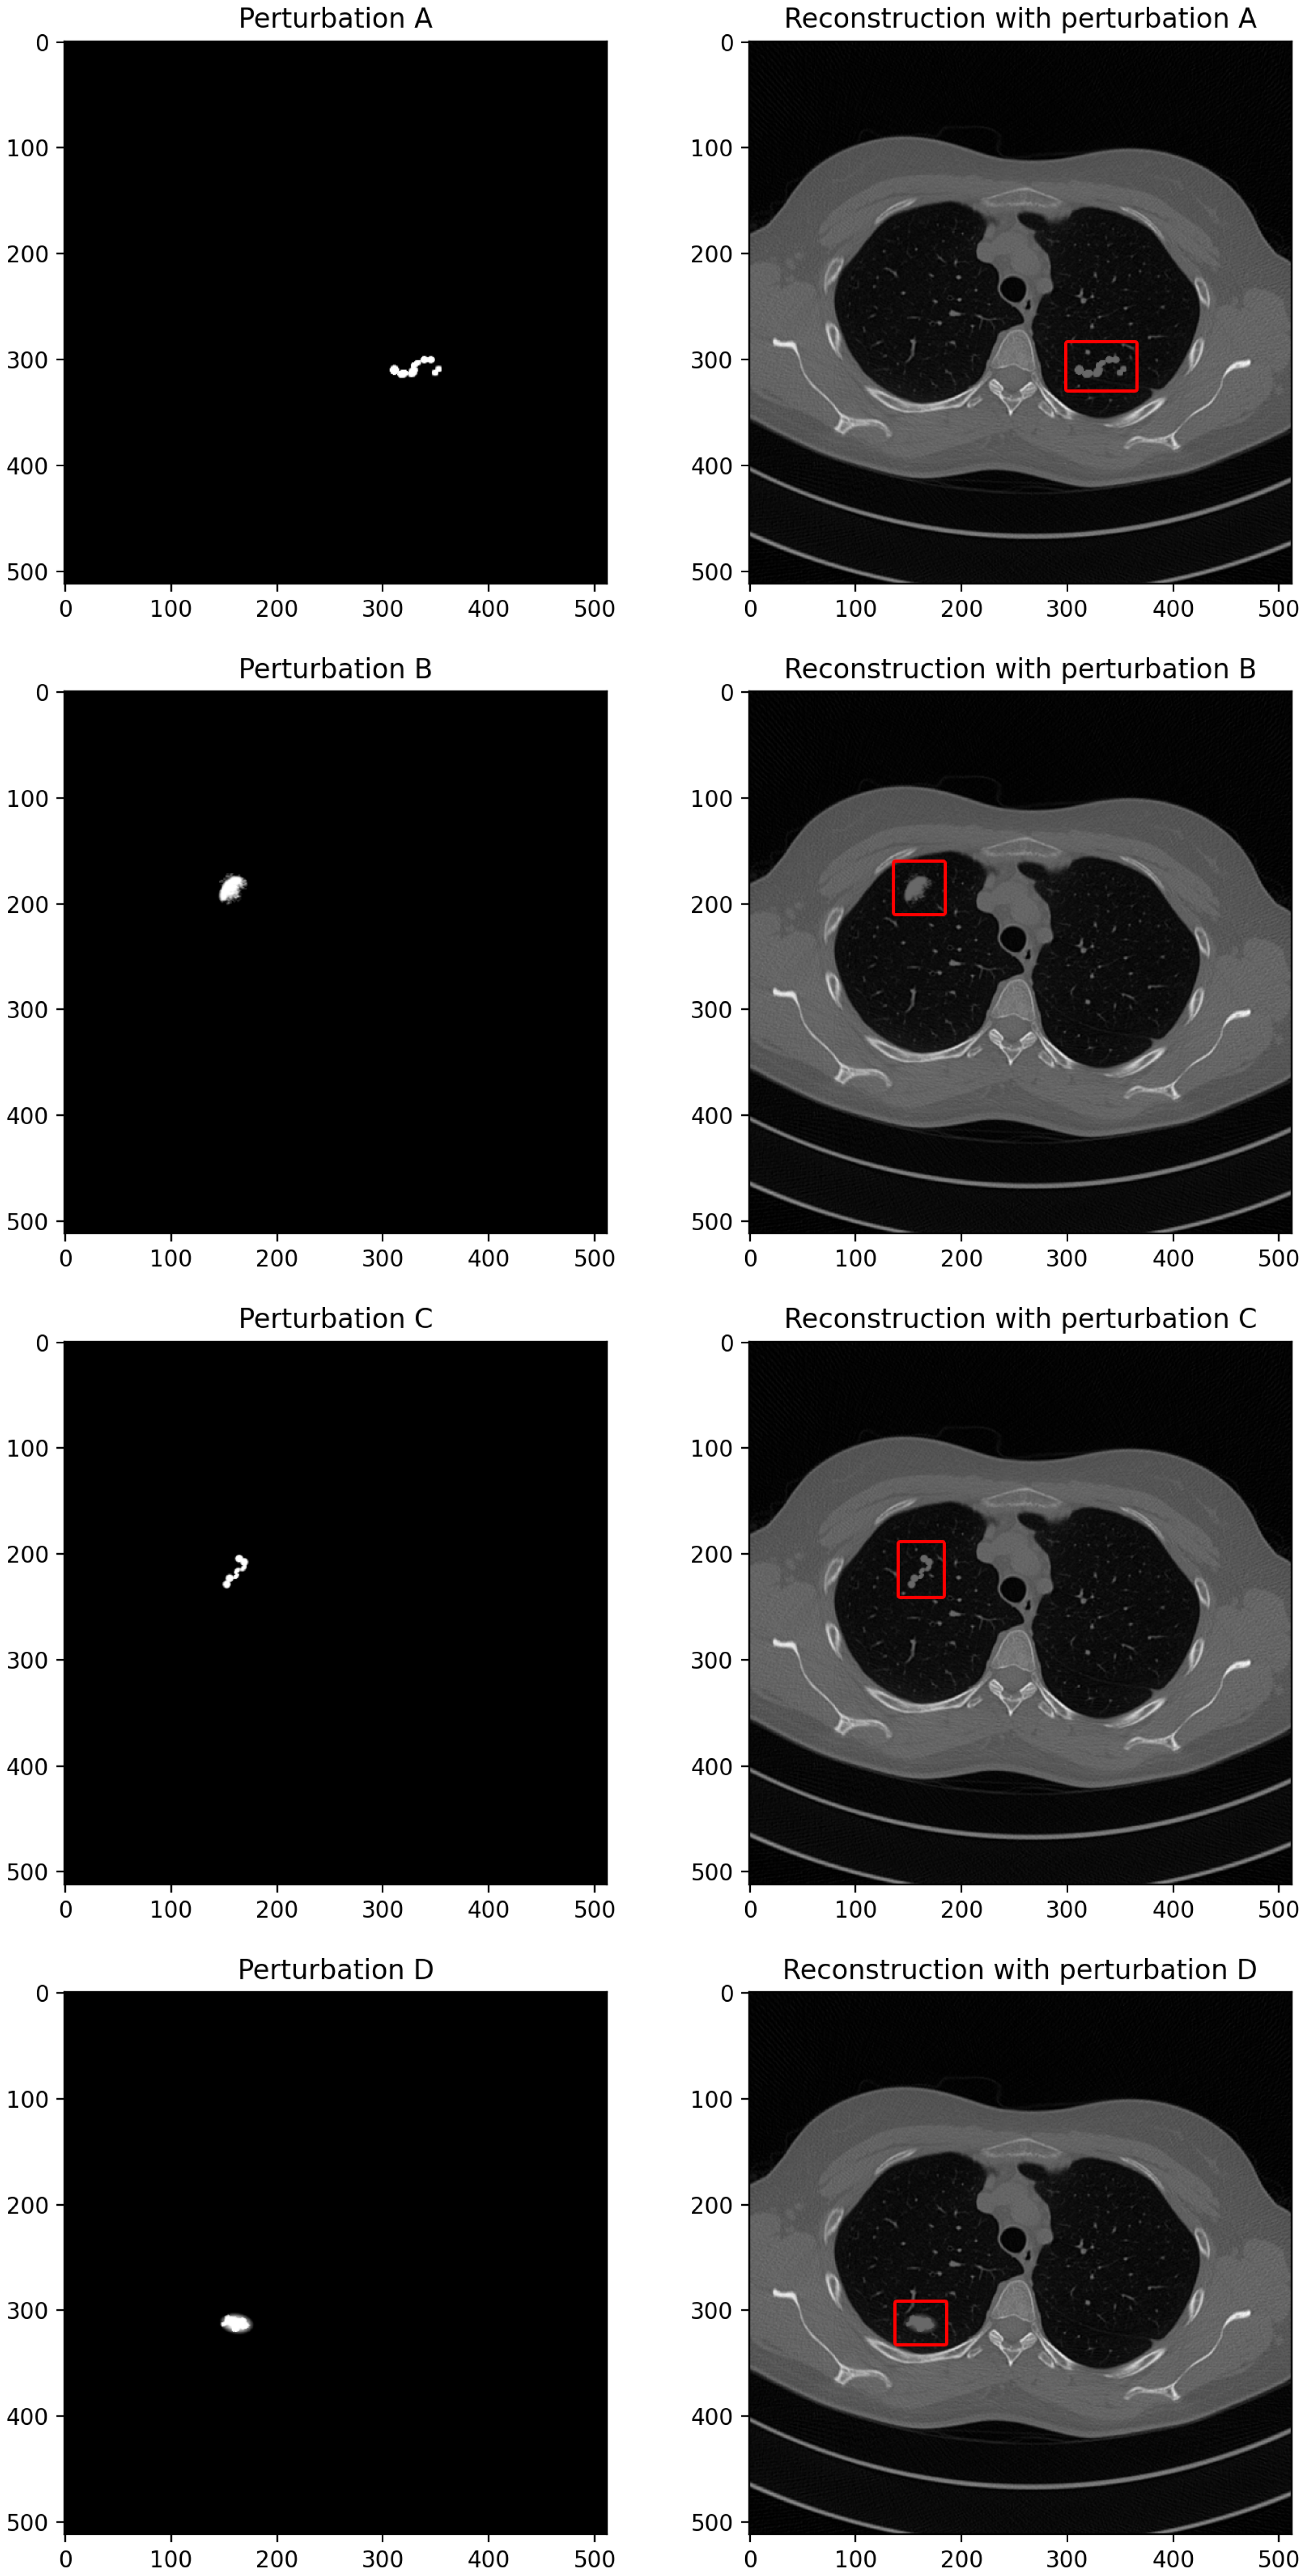

2.3. Reconstruction Perturbations

2.4. Neural Network Models